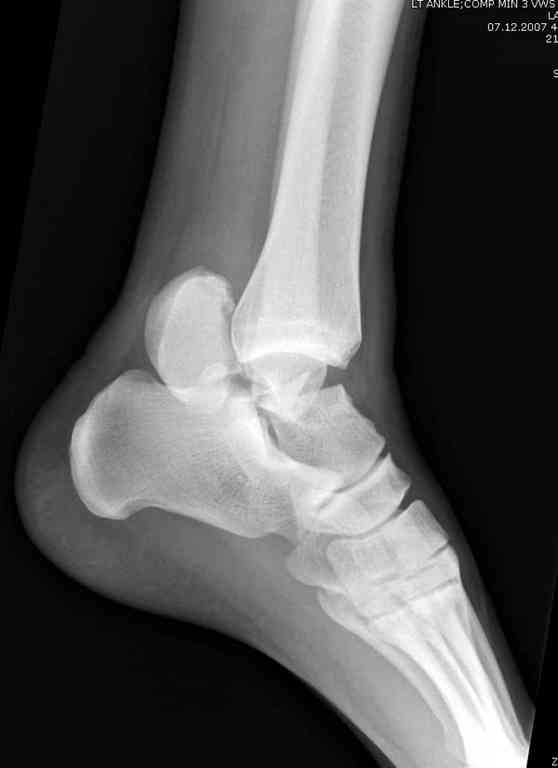

Прошу коллег помочь советом.3 дня назад поступила пациентка 23 года с переломом шейки ладьевидной справа, переломом лодыжек и заднего края б/берцовой кости со смещением и подвывихом кзади, переломом внутреннего мыщелка правого бедра без смещения. Дежурными хирургами проведена репозиция в левом г/ст суставе успешная, попытка репозиции таранной кости ухудшило положение отломков. Планируем провести повторную репозицию и фиксацию винтами. 1. Закрытая репозиция рентгенконтоль интраоперационный (аппарат Арман) ификсация из заднее-наружного доступа. 2. При неудачной закрытой репозиции переходим на открытое вправление двумя доступами медиальным и латеральным "по ходу оси таранной кости" и через дополнительный задний доступ вводим винты кортикальные 4,5 мм или 3,5 мм 3. после открытой репозиции фиксация двумя винтами через боковые доступы погружая их под суставную поверхность Сергей Зырянов ЦРБ Новосибирская область

Переломовывих тарана с повреждением медиальной стороны. Через 4 часа после поступления проведена репозиция и фиксация тарана после Irrigation&Debridment. Частичное несращение медиальной лодыжки не беспокоит, вернулся к активному образу жизни. Полная нагрузка разрешена через 11 недель. Финальные снимки через 11 месяцев.